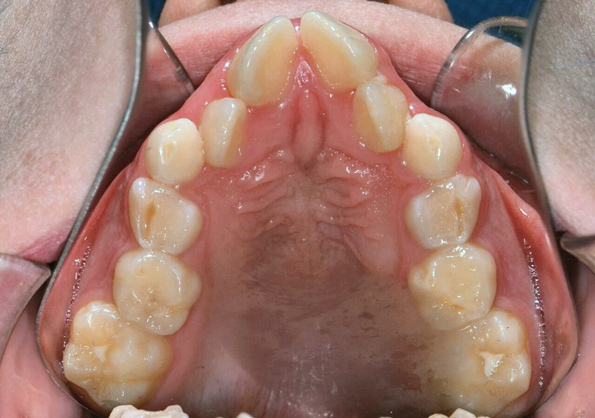

Tongue and thumb pressures also contribute to a high-vaulted palate, which can lead to mouth breathing (Figure 11).31 Additional risks exist for infection and callus development on the thumb. Ideally, the child should quit this habit by age 4, before permanent occlusal changes develop.32 Quitting can be achieved through positive reinforcement and by offering the child comfort during thumb-sucking triggers. The use of bitterants (eg, Mavala Stop, Thum, Control-It!), which are painted on or rubbed into the thumb, is another option.33 A habit breaker appliance may also be utilized if these techniques are unsuccessful. Devices such as a palatal crib, rake, or bluegrass appliance interfere with the thumb and tongue habits and allow the bite to passively close.34 The author recommends utilizing a habit breaker appliance for 6 to 9 months and maintaining reinforcement for a few months once the habit is eliminated (Figure 12 through Figure 14).

Fig 11. Severely constricted maxilla/high-vaulted palate.

Figure 11